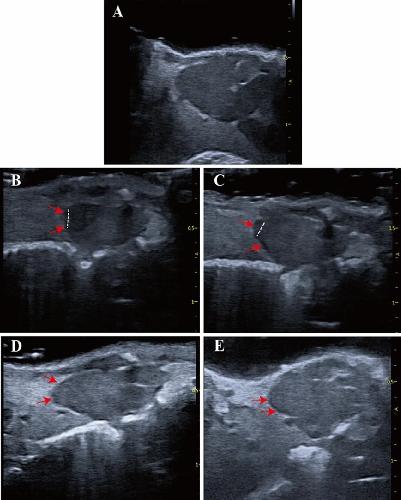

Fig. 3 Echocardiographic imaging can monitor regeneration of X. tropicalis injured hearts in a scar-free manner. A: Representative echocardiography image of the same-age nonapical resection group under B-mode. B: Representative image 5 days after apical resection. The damaged heart with a missing apex (left side of the dashed line) was clearly identified under echocardiography. C: Representative image 10 days after apical resection. D: Representative image 30 days after apical resection. E: Representative image 45 days after apical resection. The regeneration of the injured heart was able to be monitored and justified dynamically by the recovery of morphology and anatomic structure under echocardiographic imaging at 5 days, 10 days, 30 days and 45 days after apical resection. The boundary between the apical region of the regenerated heart and the surrounding tissue was clear, and no adhesion with the surrounding tissue was found at 30 days and 45 days after apical resection. Red arrow: Area of the boundary between the apical region of the regenerated heart and the surrounding tissue. Dashed line: Boundary of the regeneration zone and noninjury zone